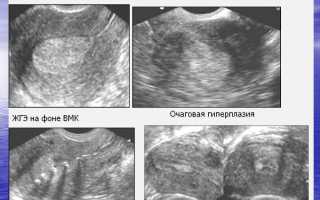

Для диагностики гиперплазии эндометрия используются различные методы. Первоначально врач проводит гинекологический осмотр, во время которого может быть выявлено увеличение матки или другие аномалии. Однако для более точной диагностики необходимы дополнительные исследования.

Одним из наиболее информативных методов является ультразвуковое исследование (УЗИ) органов малого таза. УЗИ позволяет визуализировать состояние эндометрия и выявить его утолщение. В некоторых случаях может потребоваться гистероскопия – процедура, при которой в полость матки вводится специальный инструмент с камерой, что позволяет врачу осмотреть эндометрий и, при необходимости, взять биопсию для дальнейшего гистологического исследования.